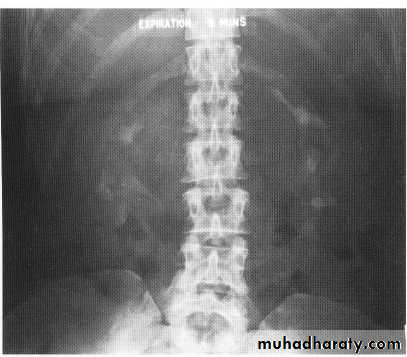

Ivu FINDING OF ACUTE OBSTRUCTION

Increasingly dense ‘obstructive’ nephrogramModest kidney enlargement (50% of patients)

Delayed caliceal opacification

PCS and uretric dilation (g.1 mild PCS dilation ,g.2 moderate PCS dilation (blunting calyces),g.3 sever dilatation within thinning of parenchyma .

Spontaneous pyelosinus extravasations (up to 24% of patients

Large kidney(partial obstruction)

Small kidney (complete obstruction)